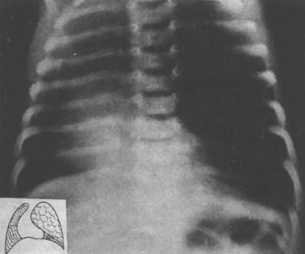

Обзорная электрорентгенограмма

Рис.

Резкое смещение срединной тени вправо вследствие

агенезии правого легкого. На бронхограмме виден переход смещенной вправо трахеи

в левый главный бронх. Бронхиальное дерево справа отсутствует.